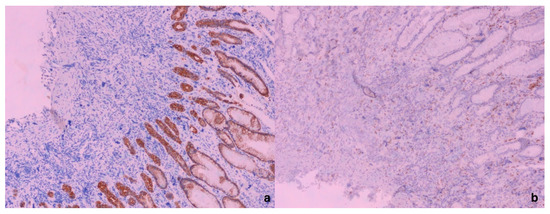

Figure 3. Giant cells—megakaryocytes immunohistochemically negative for AE1/AE3 (a) with positive internal immunohistochemical control (AE1/AE3 positivity in surface and foveolar epithelium) (×100). In (b), it is shown that giant cells, megakaryocytes, were negative for CD68, in comparison with CD68-positive macrophages (×100). Based on the performed immunohistochemical analysis and giant cell positivity for Factor VIII, CD61, and CD31, the megakaryocytic lineage of the gastric mucosa was confirmed. Because of this giant-cell immunohistochemical positivity, we suspected EMH in the gastric mucosa and, in the meantime, it was revealed that the patient had been treated for osteomyelofibrosis.

Figure 4. The microphotography of CD 71-positive cells in the stomach mucosa (erythroid lineage); ×400. In order to establish the diagnosis of EMH, in addition to the megakaryocytic lineage, erythroid lineage must also be present; hence, further immunohistochemical analysis with the CD71 antibody was performed. Immunohistochemically, CD 71-positive cells were present in the same histological sections, which proves erythroid lineage. The digestive system is a potential but uncommon site for EMH, with the gastric mucosa being particularly rare. According to the available literature, only 12 cases have been reported [1]. The EMH of the gastric mucosa in this case had a clinical and pathohistological presentation like most cases in the literature available to us [1]. The presence of giant cells in the mucosa of the digestive system is always a differential diagnostic dilemma in relation to giant tumor cells [2]. According to data from the literature, multinucleated cells can be found in the upper parts of the digestive tract as part of infectious diseases (usually of the viral type), inflammatory diseases, radiotherapy, and tumors, but benign megakaryocytes can also occur as part of myelofibrosis (megakaryocyte nuclei are larger than in reactive multinucleated stromal cells or giant cells) [2]. The proliferation of cells within the EMH in atypical places (newly formed and accumulated cells) clinically most often resemble a tumor, while symptoms depend on the localization and size of the newly formed tumefact and/or the physical symptoms of compression [1,3]. In order to establish a diagnosis of EMH, especially in non-specific places such as the digestive tract, insight into the patient’s complete medical history is very helpful [4].